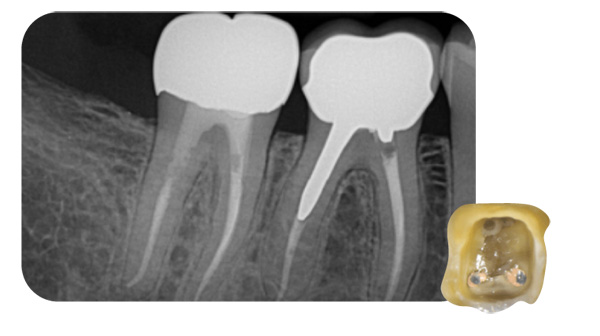

Fig. 1

Avant de commencer un retraitement, une radiographie préopératoire est obligatoire pour évaluer où le traitement précédent s’est arrêté et pourqoui il a échoué.

Il est également important de vérifier s’il y a des obstacles comme un tenon ou une lime cassée pour éviter de nouvelles complications.